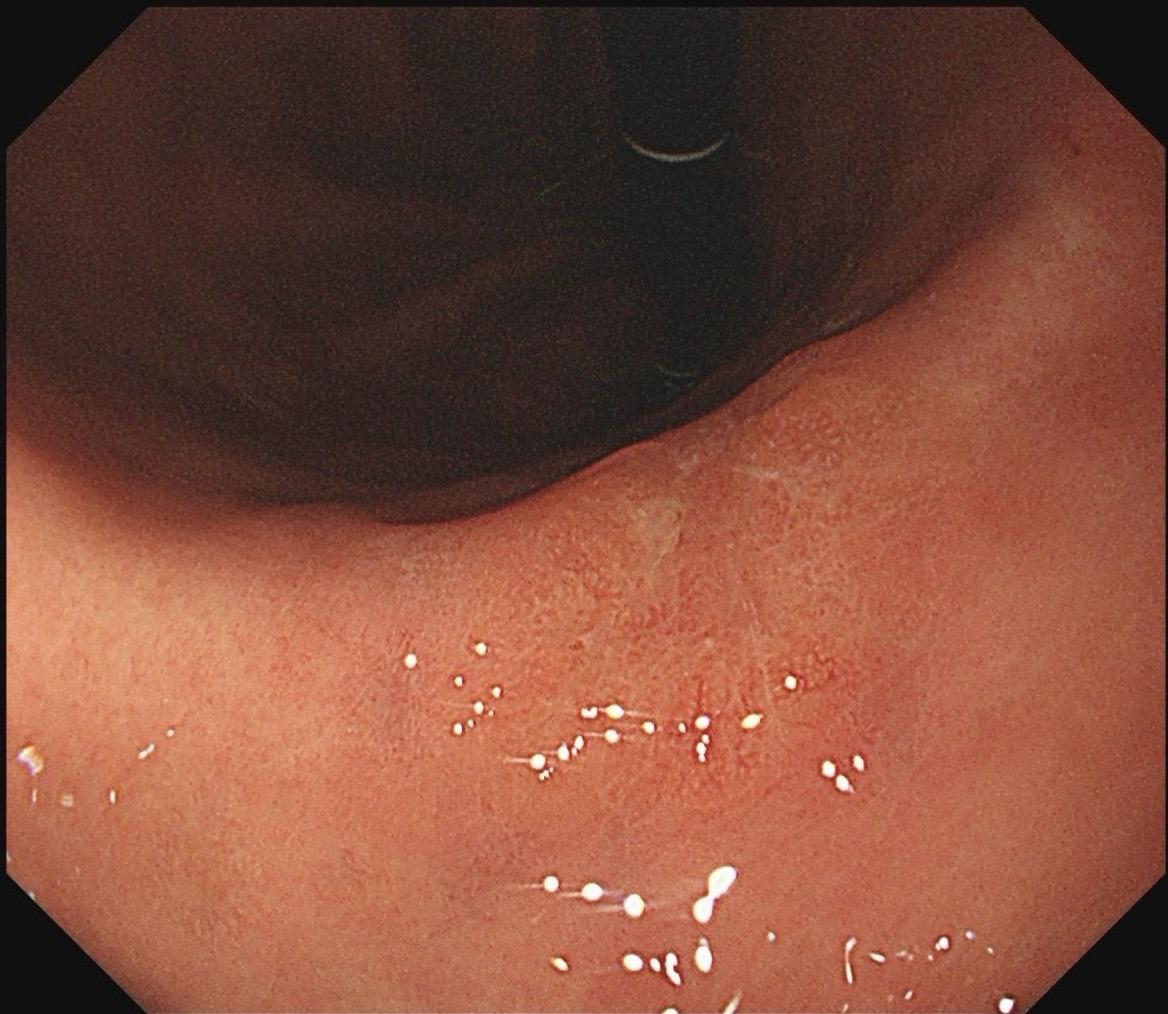

女,57岁,胃角。同事熟人,萎缩背景,色调淡黄,中央浅凹陷,腺管小而密集。